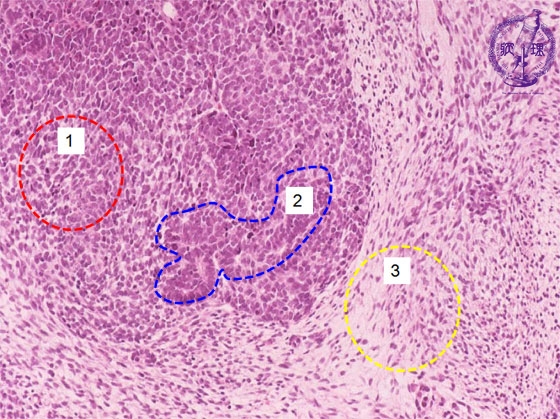

- (16)Nephroblastoma (Wilms tumor)

Microscopic findings ( HE, middle power view): Th tumor is composed of (1) blastemal, (2) organoid and (3) stromal elements (each shown by dotted lines).